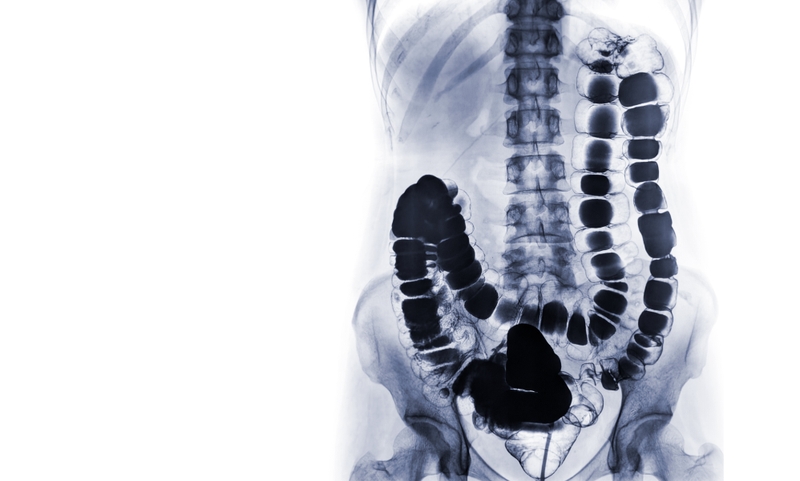

Kỹ thuật chụp X quang đại tràng sử dụng tia X, phát ra từ máy chụp X quang để chiếu xuyên qua đại tràng. Sau đó, hình ảnh đại tràng bên trong cơ thể được ghi lại trên tấm phim hoặc tấm cảm biến. Nhờ đó, các bác sĩ có thể quan sát được hình ảnh cấu trúc bên trong đại tràng. Đây là những hình ảnh sẽ không thể quan sát được bằng mắt thường.

Một số trường hợp chống chỉ định dùng Barium, không khí sẽ được bơm vào đại tràng nhằm mở rộng lòng ruột để cải thiện chất lượng hình chụp X quang. Kỹ thuật này được gọi là kỹ thuật chụp X quang đại tràng tương phản không khí, dùng thay thế khi không phù hợp để áp dụng chụp X quang đại tràng cản quang.